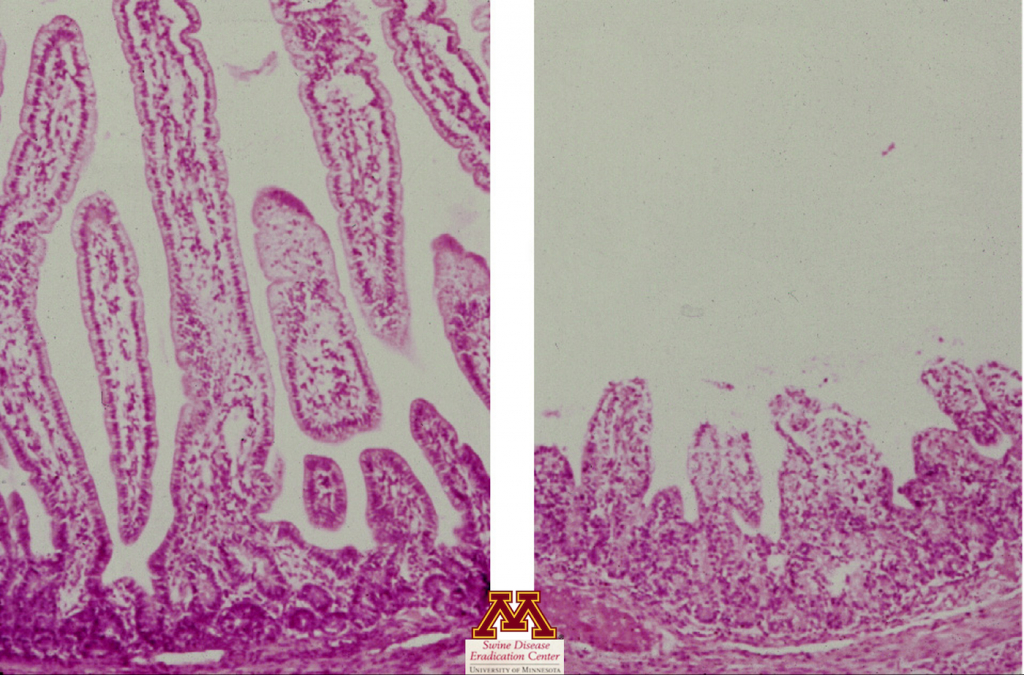

Histopatologia

- Ocenia obecność zmian w tkankach (zanik kosmków jelita cienkiego), które mogą sugerować obecność choroby.

- Potwierdzenie zaniku kosmków jelitowych sugerującego wirusowe zapalenie jelit